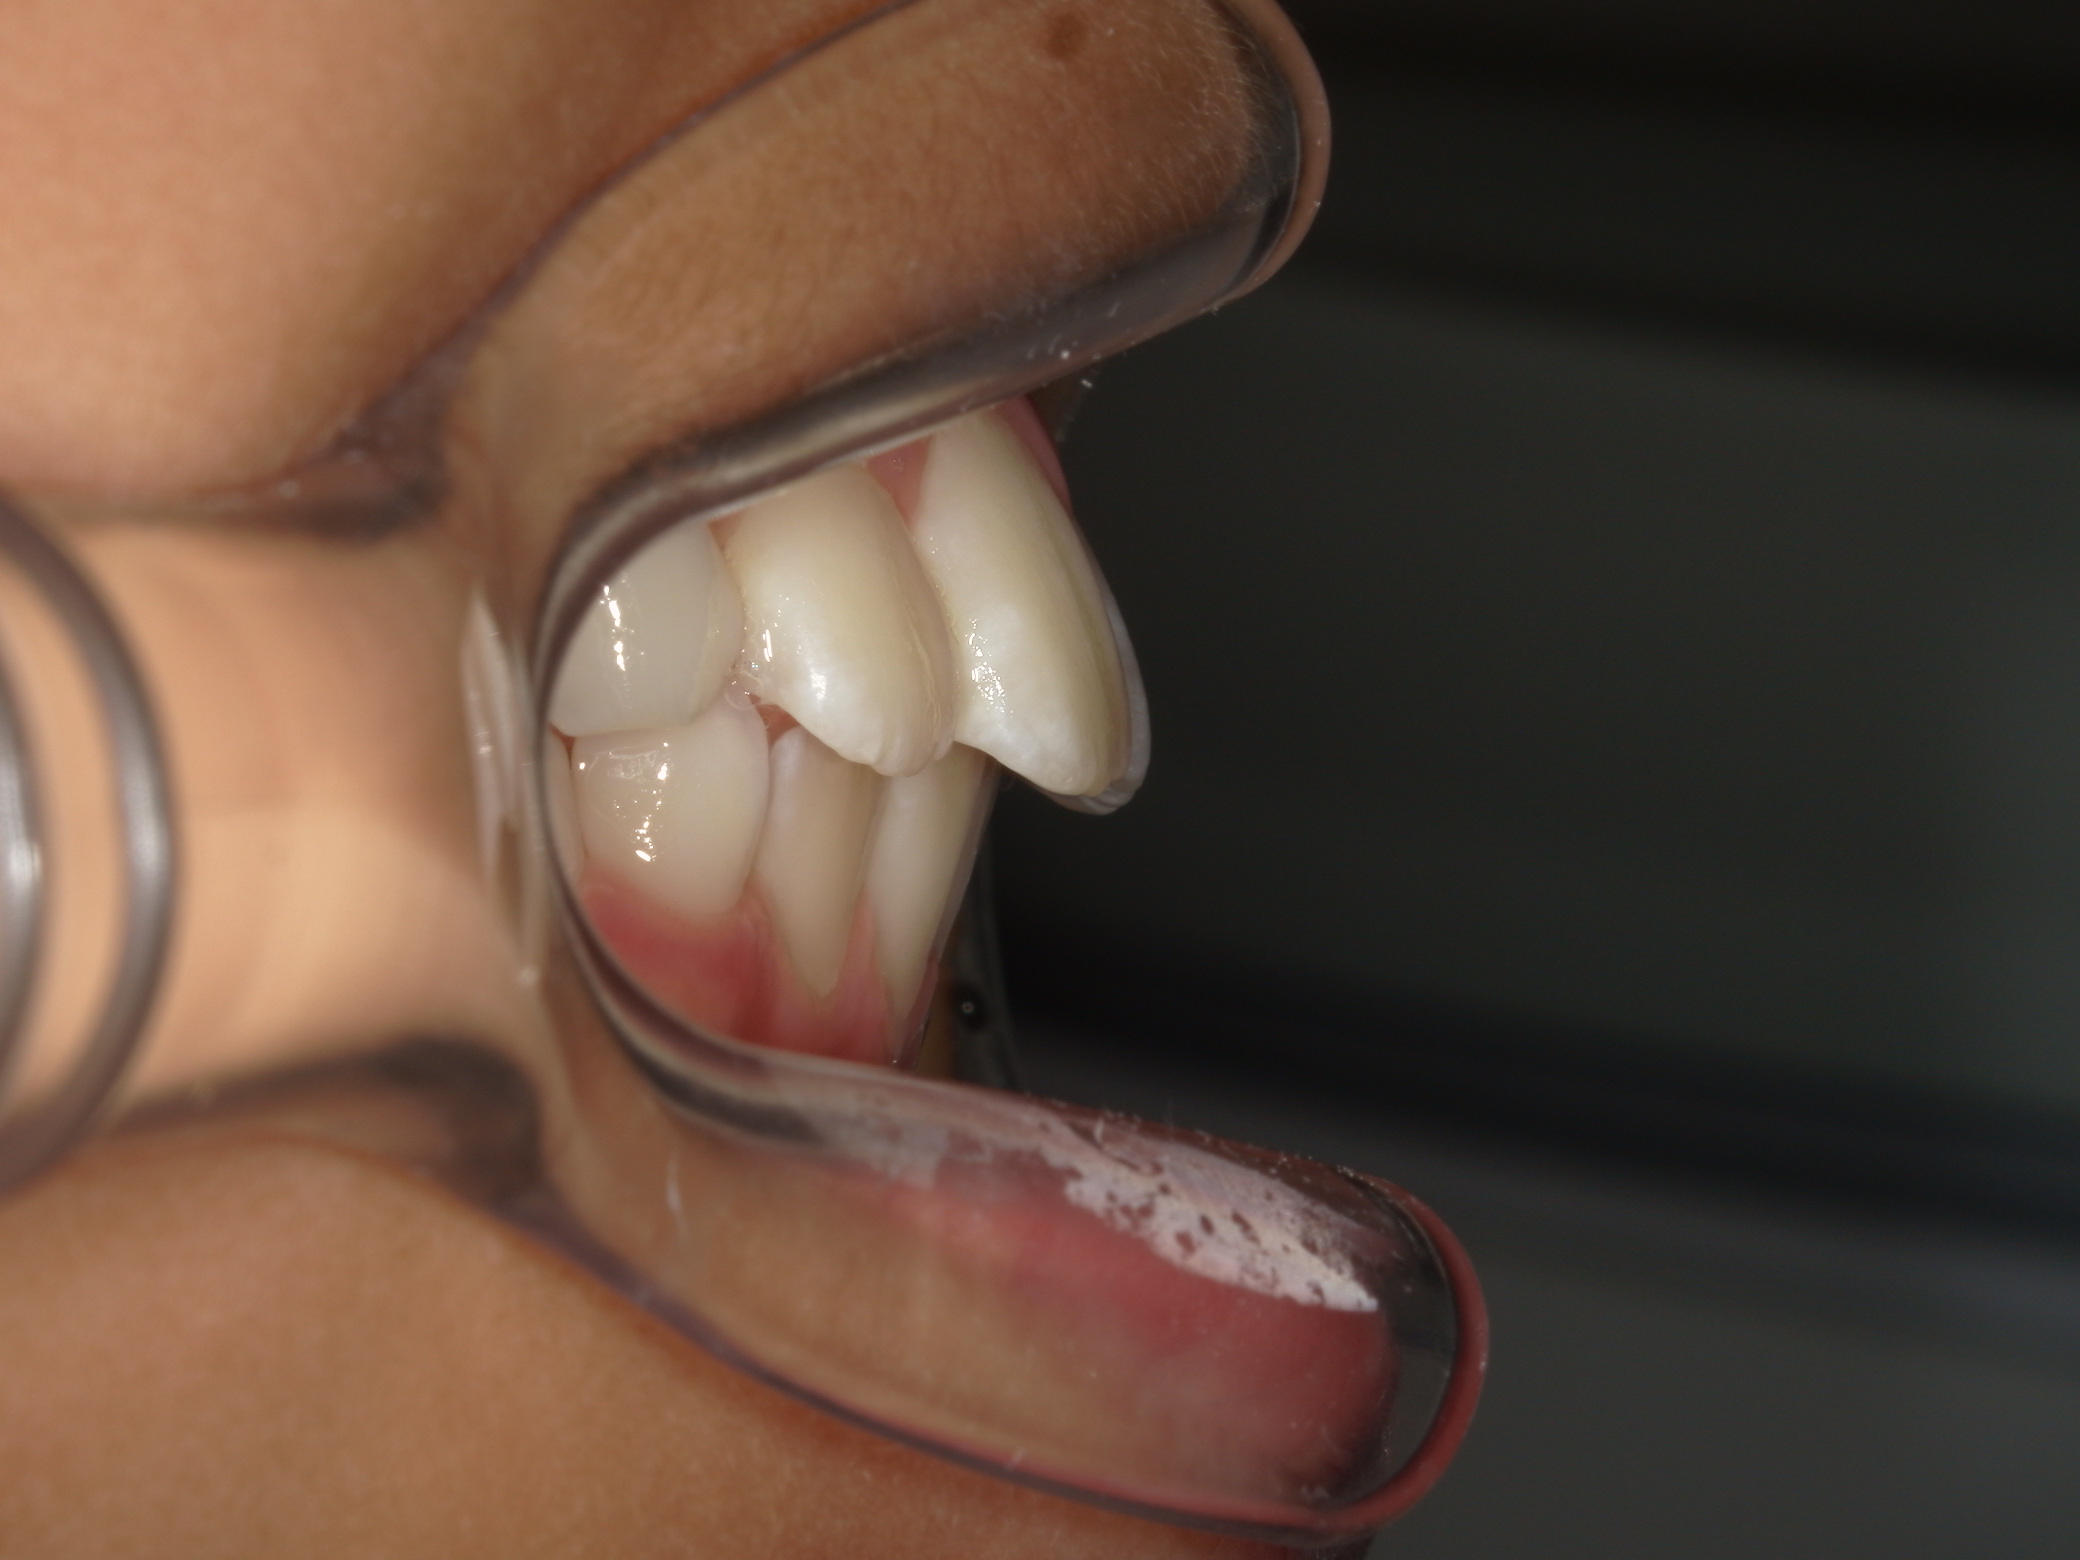

早期矯正治療 交叉咬合症例

主訴 | 前歯の咬み合わせが逆になっており、歯根や歯肉への影響を懸念されて来院された患者様です。 |

---|---|

診断結果 | 8歳9か月の男児。 上下前歯の交叉咬合と、下顎前歯部の歯肉退縮傾向が認められました。 |

治療内容 |

|

治療後の経過 |

治療期間 | 動的治療期間:3年7か月 通院回数:20回 |

治療費用 | 460,000円(税別) |